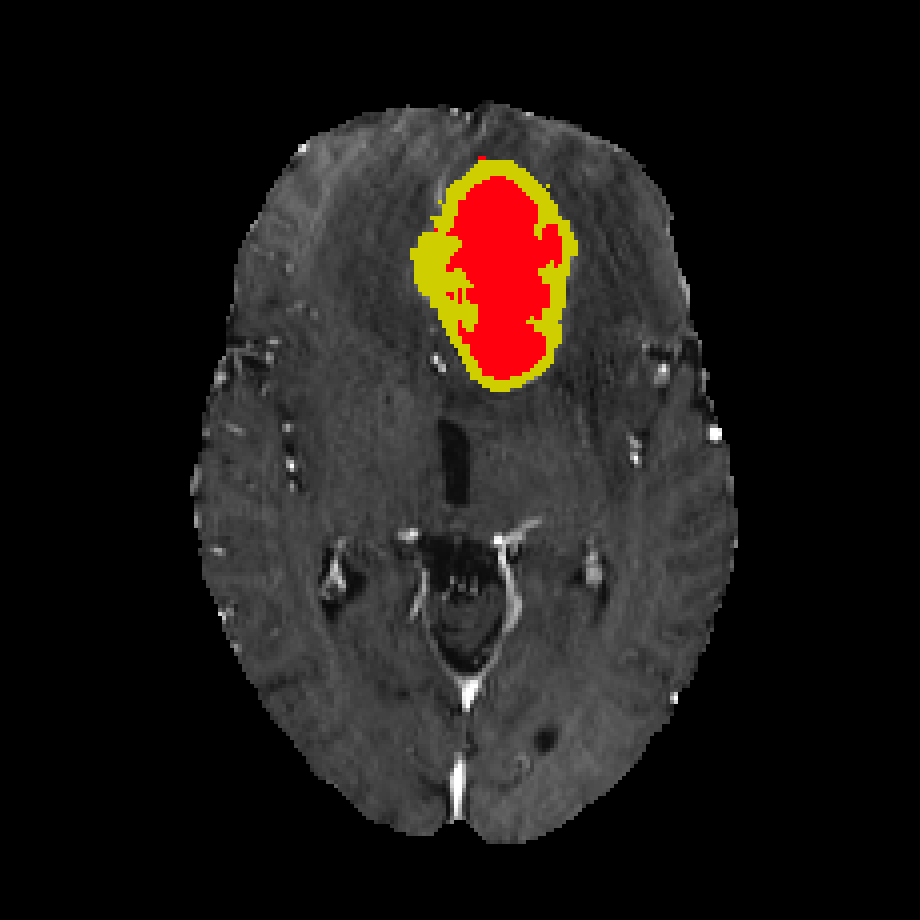

Furthermore, experienced radiologists often analyze multimodal data in clinical practice by designating a primary modality and several auxiliary modalities for pathological diagnosis. This approach is exemplified in the BraTS challenge (Menze et al., 2014) (Figure 2). In this challenge, the segmentation target was the different areas of glioblastoma, which is the most common type of brain malignancy. Glioblastoma is characterized by its resistance to treatment and poor prognosis, making it a critical focus for advancements in medical imaging and treatment strategies(Li et al., 2019). Human annotators primarily employ the T2 modality222T1, T1CE, T2, and FLAIR represent four modalities generated by MRI imaging technology. for segmenting the edema region while using the FLAIR modality to verify the presence of edema and other fluid-filled structures. Subsequently, the tumor core (TC) is identified through the combined use of T1CE and T1 modalities. The expertise of these radiologists suggests that specific mapping relationships exist between modalities and target areas. Certain modalities facilitate the identification of particular area boundaries, while others serve as supplementary aids. Gleaning insights from this expert knowledge and incorporating it as an inductive bias can potentially reduce the complexity of learning relationships between modalities and corresponding regions. A similar example of adding priors to reduce learning difficulty is DetexNet (Liu et al., 2020), which simplifies low-level representation patterns by embedding expert knowledge.

To describe task decomposition more clearly, we take BraTS2020 as an example. As illustrated in Fig.3, the original multi-target task is divided into four distinct sub-tasks. The sub-tasks involve utilizing FLAIR as the primary modality for segmenting the whole tumor (WT) region, employing T1 as the primary modality for segmenting both the tumor core (TC) and the enhanced tumor (ET), leveraging T2 as the primary modality for segmenting the WT and TC regions and adopting T1CE as the primary modality for segmenting the TC and ET regions. This task decomposition is based on expert prior knowledge, which suggests that the selected primary modalities contain the most informative features for accurately segmenting their respective target regions. In addition, to test the performance of different decompositions, we designed ablation experiments to compare several different decomposition methods, as detailed in Section 4.